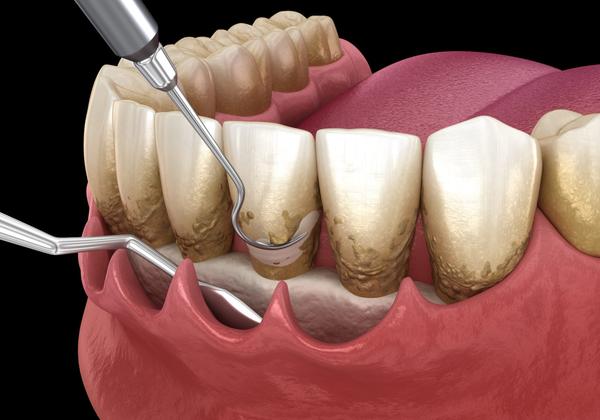

Scaling is a type of cleaning that uses a speci...